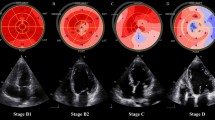

Prognostic utility of RV GLS

We found that RV GLS was significantly associated with ARDS. Additionally, SpO2, CRP, and age were independent predictors of ARDS in a multivariate analysis. Our findings may explain those of previous studies, which demonstrate that RV strain predicts mortality and the need for intubation and mechanical ventilation, if mortality is driven by ARDS [11,12,13,14,15,16,17,18]. Early subclinical RV dysfunction may be a result of direct cardiomyocyte injury caused by SARS-CoV2, or a secondary consequence of pulmonary disease or systemic inflammation leading to RV strain and increased afterload [7, 11, 25]. TAPSE, S’, and RV FAC were not associated with ARDS, consistent with findings by Li et al. who demonstrated superiority of RV GLS to these conventional parameters in predicting COVID-19 outcomes [11]. This may be due to differences in the ability of these parameters to more completely assess RV performance, as RV GLS measures deformation throughout the entire RV free wall, in contrast to TAPSE and S’ which represent only basal longitudinal movement. Additionally, strain analysis reflects maximal and minimal values of deformation throughout the cardiac cycle, which may not be reflected in the end-systole and end-diastole frames used to measure RV FAC [11, 26, 27].

CHF was predicted by LV GLS, LV EF, and RV FAC in a bivariate analysis, but not by LV GLS when controlling for the latter two. This suggests a bimodal distribution of illness severity, wherein patients with mild infection have subclinical ventricular dysfunction and generally do not develop CHF. Conversely, those with severe infection are more prone to experiencing early, substantial cardiac involvement with greater risk of CHF.